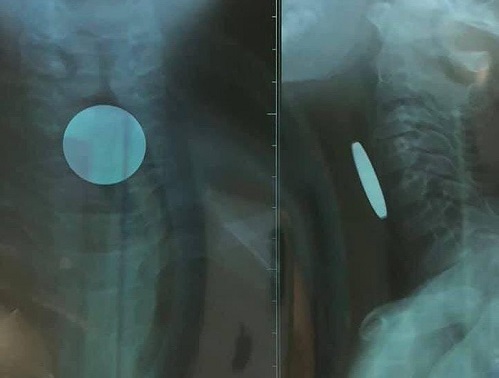

Hình ảnh đồng xu đoạn thực quản cổ trên phim X-quang - Ảnh: Tiền Phong |

Bác sĩ Nguyễn Hoàng Tùng, khoa Tai Mũi Họng, cho biết bệnh nhi vào viện trong tình trạng toàn thân ổn định và bé kêu đau vùng cổ. Các bác sĩ tiến hành thăm khám và chụp X-quang, kết quả cho thấy bé bị dị vật (đồng xu) đoạn thực quản cổ có đường kính 24 mm.

Đồng xu này có đường kính 24 mm - Ảnh: Tiền Phong |